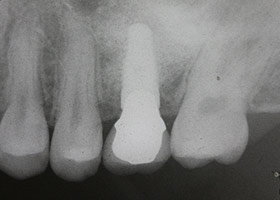

水雷射植牙技術,由字面上來解釋是水和雷射的結合,是利用特殊雷射波長使水分子激發成為具有高速動能的狀態,利用水分子作為組織切割之媒介的新科技。傳統治療中,鑽骨會產生熱或微裂的現象,而使得病患感到不適,但應用流體動力切割的新技術不易產生熱與震動微裂,讓整個治療過程疼痛大幅降低。

- 比傳統植牙縮減部分療程,且不需要翻開牙齦瓣膜就可鑽入植體。

- 雷射微創植牙是使用低能量牙科專用雷射,使用雷射可以大幅降低植牙時的疼痛及不適感,可減緩患者心理的恐懼感。